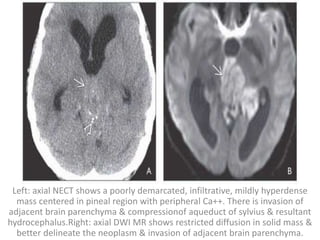

Left: axial NECT shows a poorly demarcated, infiltrative, mildly hyperdense

mass centered in pineal region with peripheral Ca++. There is invasion of

adjacent brain parenchyma & compressionof aqueduct of sylvius & resultant

hydrocephalus.Right: axial DWI MR shows restricted diffusion in solid mass &

better delineate the neoplasm & invasion of adjacent brain parenchyma.